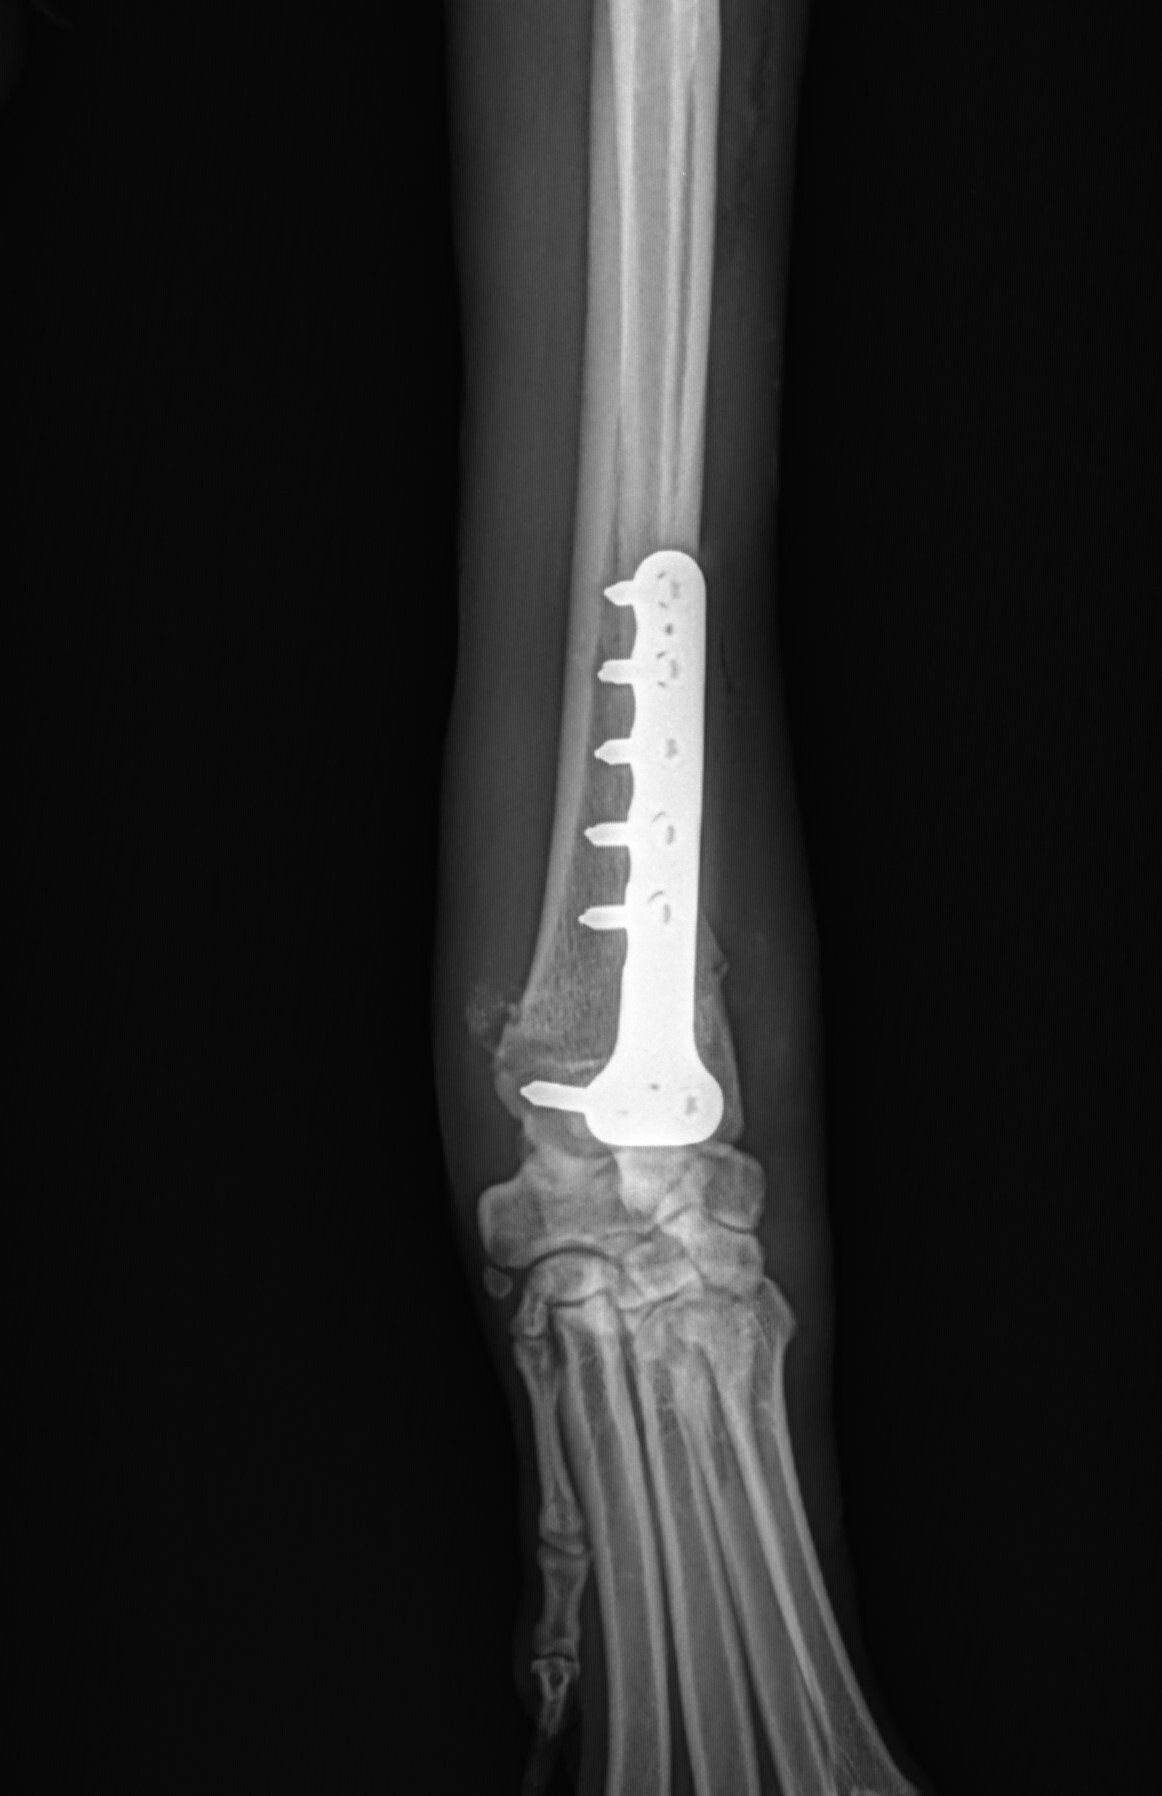

- “Plating” involves attaching a flat stainless steel plate to the bone using screws on either side of the fracture.

Below are x-rays of just a few orthopedic surgeries before and after that Dr. Gose has performed.